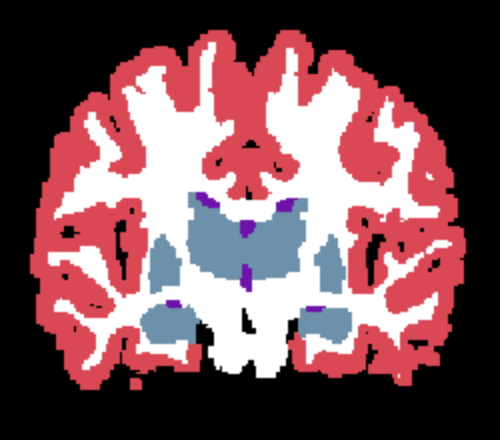

| (a) Input | (b) Ground Truth | (c) Supervised | (d) SAMSEG | (e) Naive SynthSeg | (f) Learn2Synth |

Results. Qualitative segmentation results are presented in Figure 3 and quantitative results are summarized in Table 5. Figure 3 shows that Learn2Synth produces cleaned and more accurate segmentation results compared to SAMSEG and naive SynthSeg, which is further validated by the higher Dice scores reported in Table 5. Learn2Synth also obtains higher Dice scores than the two SynthSeg variants that incorporate real data. These results highlight the effectiveness of Learn2Synth in enhancing segmentation quality for complex real-world data.